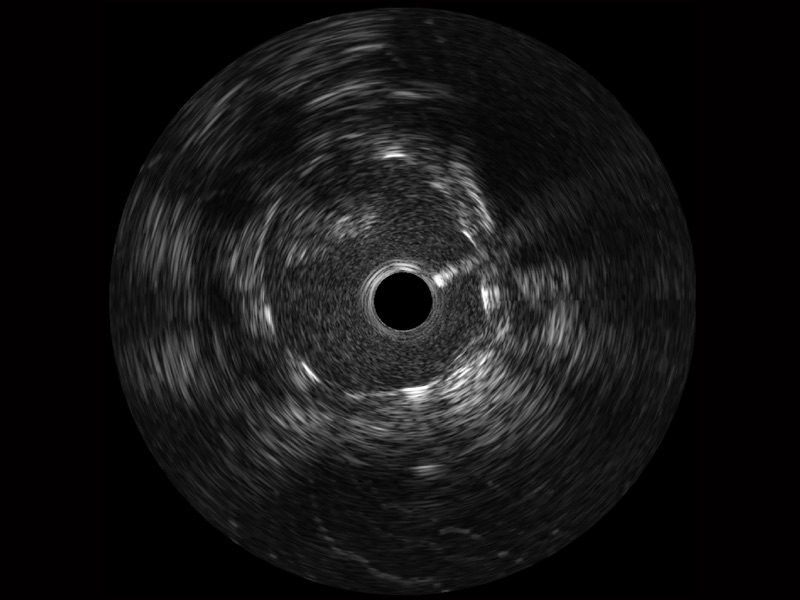

玖鼎集团宽频IVUS图像

对比传统IVUS导管成像,玖鼎集团宽频IVUS图像的近场支架梁显影更细腻,远场中膜外血管仍清晰可辨,兼顾远中近,兼顾分辨力与穿透深度